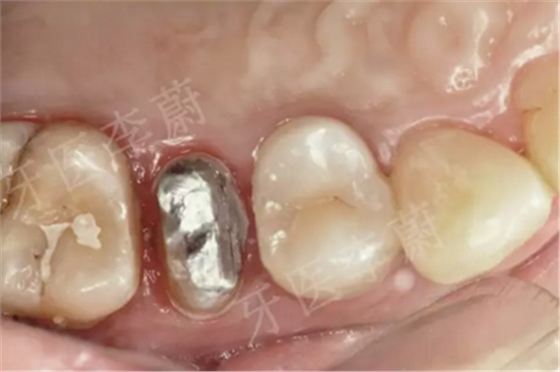

15牙金屬分裂樁口內(nèi)粘接